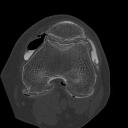

Pingback: UltraCameraStores.info » Blog Archive » DICOM foto’s linkerknie